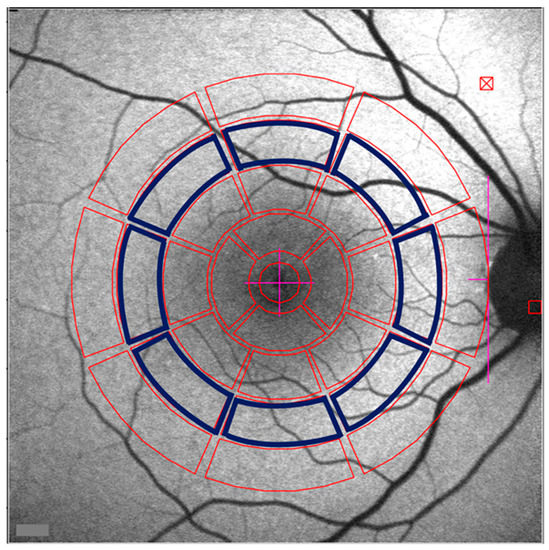

- Han, L.; de Carvalho, J.R.L.; Parmann, R.; Tezel, T.H.; Chang, S.; Sharma, T.; Sparrow, J.R. Central Serous Chorioretinopathy Analyzed by Multimodal Imaging. Transl. Vis. Sci. Technol. 2021, 10, 15. [Google Scholar] [CrossRef] [PubMed]

- Duncker, T.; Lee, W.; Jiang, F.; Ramachandran, R.; Hood, D.C.; Tsang, S.H.; Sparrow, J.R.; Greenstein, V.C. Acute zonal occult outer retinopathy: Structural and Functional Analysis Across the Transition Zone Between Healthy and Diseased Retina. Retina 2018, 38, 118–127. [Google Scholar] [CrossRef]

- Boudreault, K.A.; Schuerch, K.; Zhao, J.; Lee, W.; Cabral, T.; Yannuzzi, L.A.; Tsang, S.H.; Sparrow, J.R. Quantitative Autofluorescence Intensities in Acute Zonal Occult Outer Retinopathy vs Healthy Eyes. JAMA Ophthalmol. 2017, 135, 1330–1338. [Google Scholar] [CrossRef]